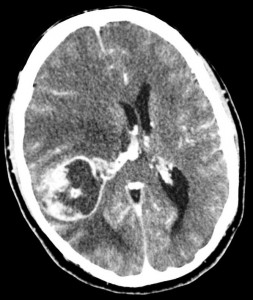

El método diagnóstico de primera elección en procesos de instauración aguda en el encéfalo es el TC craneal. La Tomografía Computarizada es una prueba rápida, barata y de alta disponibilidad que nos permite valorar de forma rápida y con alta sensibilidad las posibles lesiones. En este caso, el TC nos permite descartar si el paciente sufre un cerebrovascular.